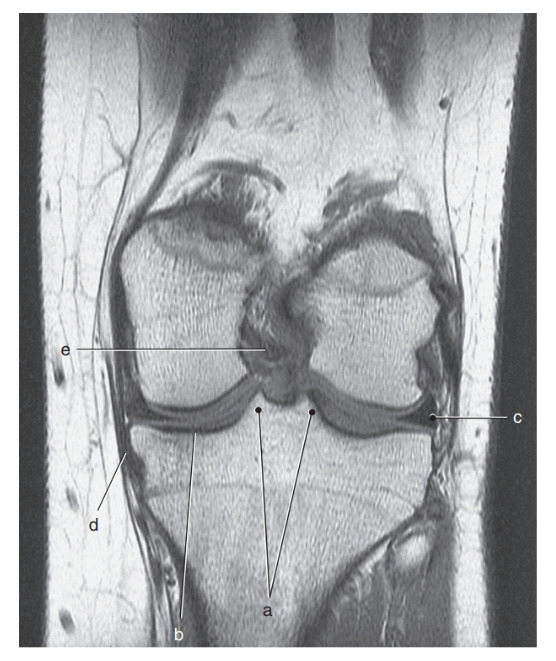

What is c ?

anterior cruciate ligament

In what orientation would a tear of the collateral ligaments of the knee be best visualized?

coronal

lateral meniscus

What is d ?

posterior cruciate ligament